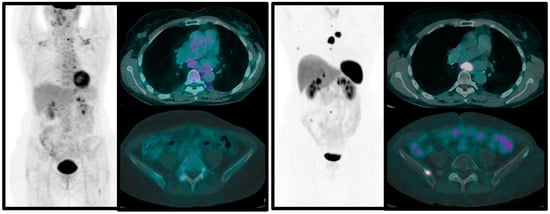

- Zidan, L.; Iravani, A.; Kong, G.; Akhurst, T.; Michael, M.; Hicks, R.J. Theranostic implications of molecular imaging phenotype of well-differentiated pulmonary carcinoid based on 68Ga-DOTATATE PET/CT and 18F-FDG PET/CT. Eur. J. Nucl. Med. Mol. Imaging 2021, 48, 204–216. [Google Scholar] [CrossRef]

- Albano, D.; Dondi, F.; Bauckneht, M.; Albertelli, M.; Durmo, R.; Filice, A.; Versari, A.; Morbelli, S.; Berruti, A.; Bertagna, F. The diagnostic and prognostic role of combined [18F]FDG and [68Ga]-DOTA-peptides PET/CT in primary pulmonary carcinoids: A multicentric experience. Eur. Radiol. 2022, 33, 1–11. [Google Scholar] [CrossRef] [PubMed]